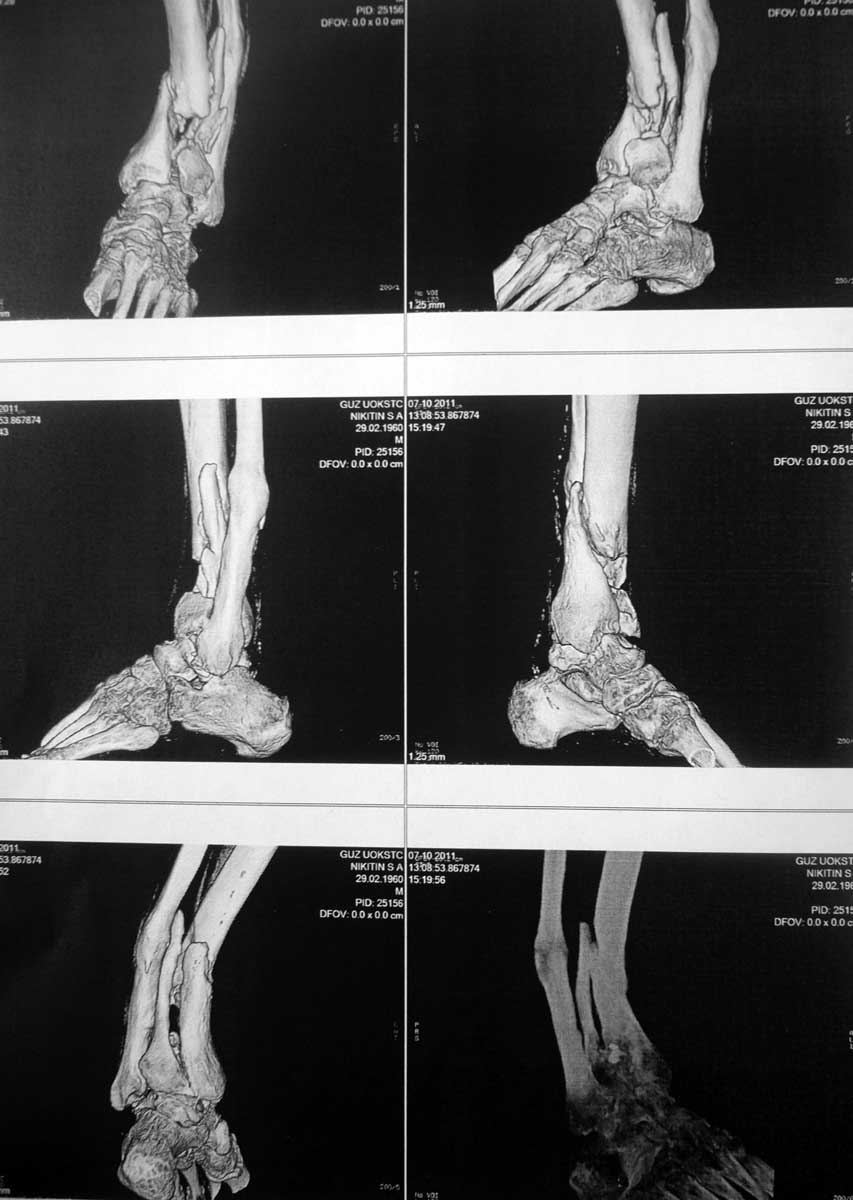

[Ortho] Ложный сустав голени

Пациент 51 год травма 29.12.09, лечился консервативно. К нам обратился вчера. объективно:

ходит без опоры на левую ногу, варусная деформация голени около 20 градусов, патологическая

подвижность в зоне перелома. Что по вашему мнению можно сделать для лечения этой патологии.